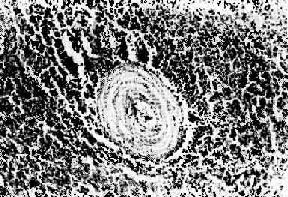

红斑性狼疮之脾病变

图4-12 红斑性狼疮之脾病变

脾小体中央细动脉壁呈洋葱皮样结构